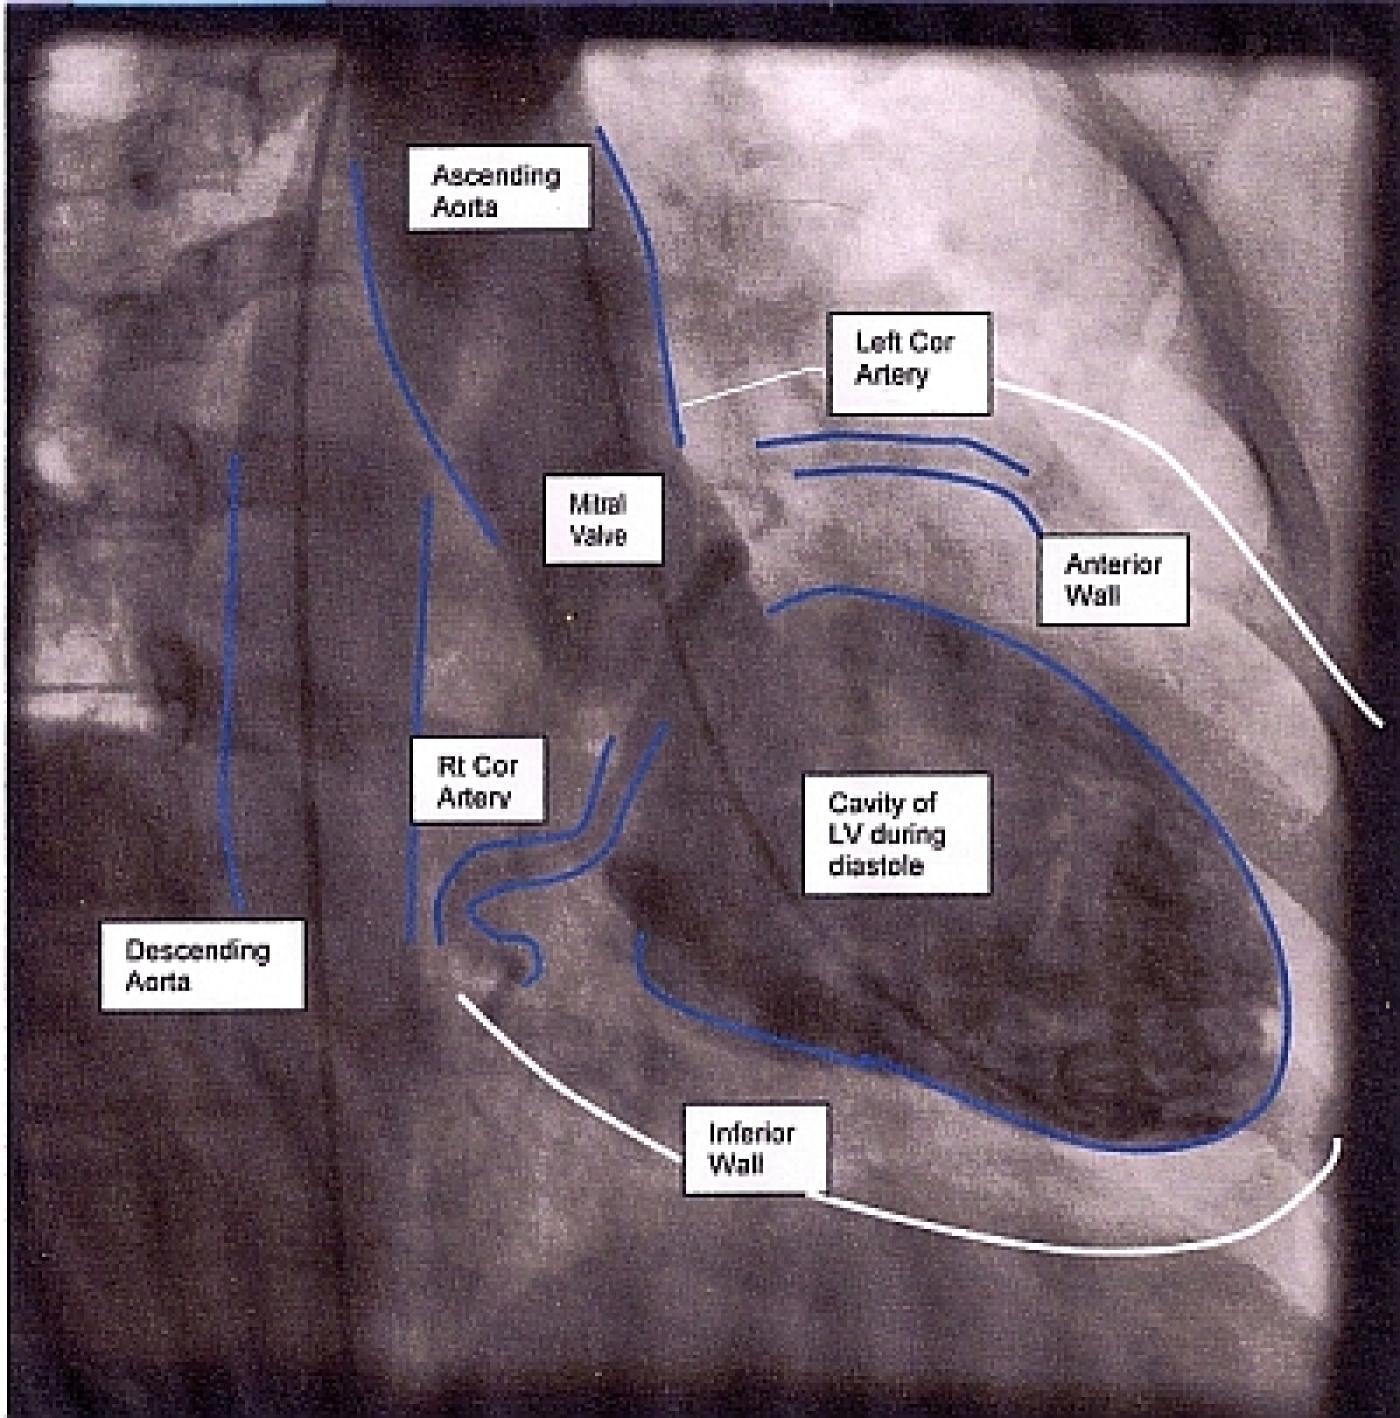

Left ventriculography. (A) Left ventriculography showing catheter

Cardiac catheterization demonstrating left ventriculography in diastole Catheters Used For Left Ventriculography Catheterization of the left side of the heart is done to obtain information about the heart chambers on the left side (left atrium and left ventricle), the. This widely used method requires separate preformed catheters for the right and left coronary arteries (see the images below). Left heart catheterization is done via femoral, subclavian, radial, or brachial artery puncture, with. Catheters Used For Left Ventriculography.